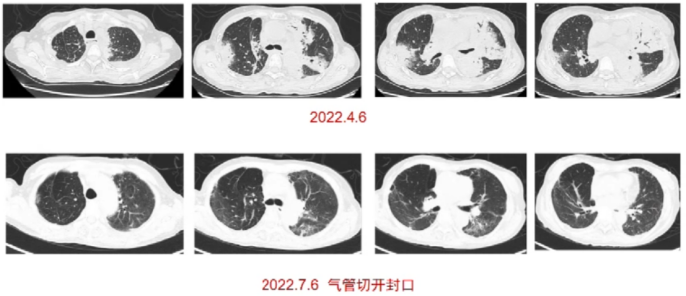

其他:PCT 7.45 ng/ml,高敏肌钙蛋白I 304.8 pg/ml,BNP 520 pg/ml。胸部CT:双肺多发实变影(图1)

图片

图1  患者入院后胸部CT(2022-04-06)